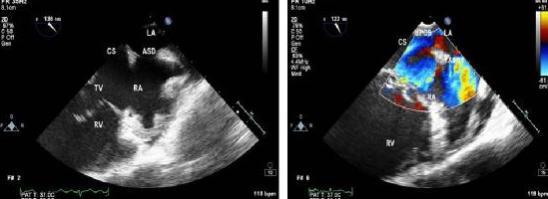

3、超声心动图检查可显示房缺的位置和大小,这是诊断房缺的有力证据。

5.原发孔未闭与继发孔未闭的临床表现极为相似。房缺患者心尖部闻及反流性收缩期杂音,心电轴左偏,P-R间期延长或伴不完全性右束支传导阻滞,应高度怀疑原发孔未闭。二维超声或右心导管检查示缺损的部位较低,接近三尖瓣口附近。右心房血氧含量增高,右心室更高,多普勒彩超或心血管造影可明确房室通道或二尖瓣关闭不全等改变。